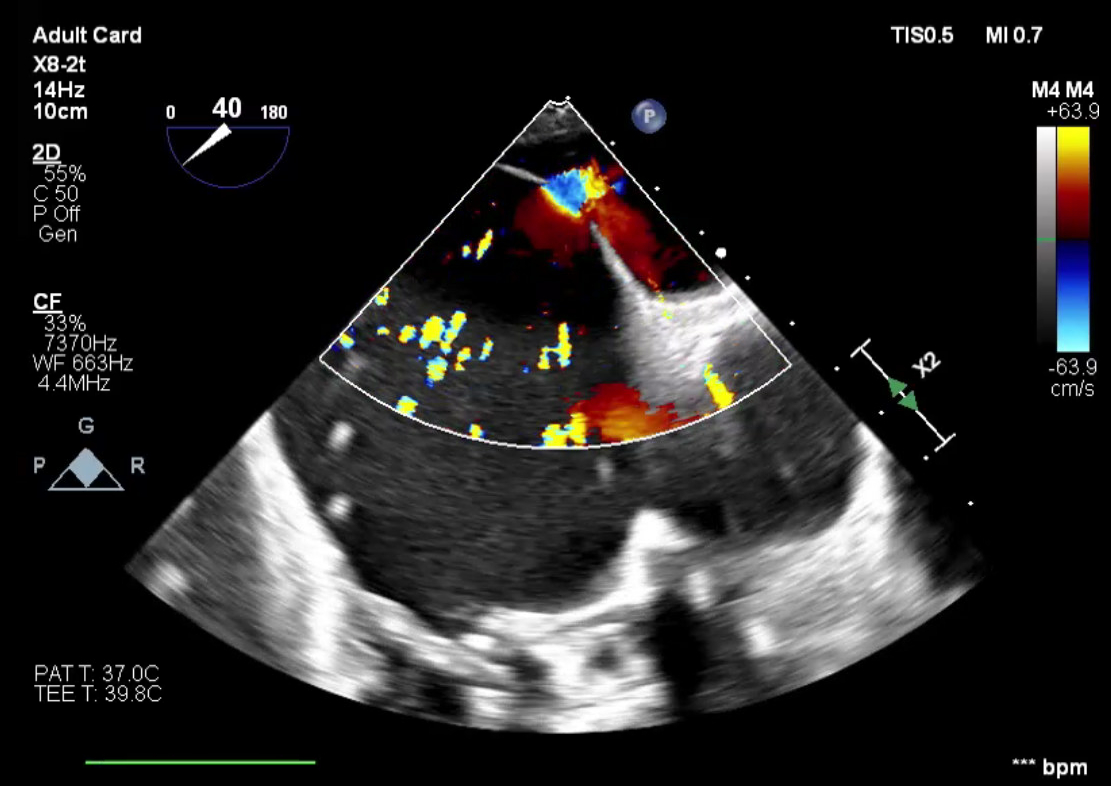

Abstract Body (Do not enter title and authors here): Case Description: A 54-year-old male with ESRD on hemodialysis, tricuspid valve endocarditis status post bioprosthetic valve replacement, and atrial fibrillation status post catheter ablation one month prior, underwent elective Watchman device implantation. Following successful device placement, the patient continued to require ventilator support. Intra-procedural TEE revealed a known iatrogenic atrial septal defect (iASD) from prior ablation with a moderate right-to-left shunt and a peak gradient of 16 mmHg. The bioprosthetic tricuspid valve demonstrated severe stenosis. Additional findings included moderate-to-severe tricuspid regurgitation, a severely dilated right atrium, and preserved left ventricular ejection fraction. The patient remained ventilator-dependent and developed septic shock within 24 hours secondary to pneumonia. Despite dialysis and antibiotic therapy, hypoxia persisted. The right-to-left shunt across the iASD, driven by elevated right atrial pressure from severe tricuspid stenosis, was identified as a major contributor. On hospital day 9, the patient underwent transcatheter tricuspid valve replacement. Following the procedure, he improved rapidly, was extubated within 48 hours, and was discharged four days later, off supplemental oxygen and ambulating with support. At 45-day follow-up, he remained asymptomatic. TEE showed a well-functioning tricuspid prosthesis, moderately dilated right atrium, and two small ASDs with predominantly left-to-right flow.